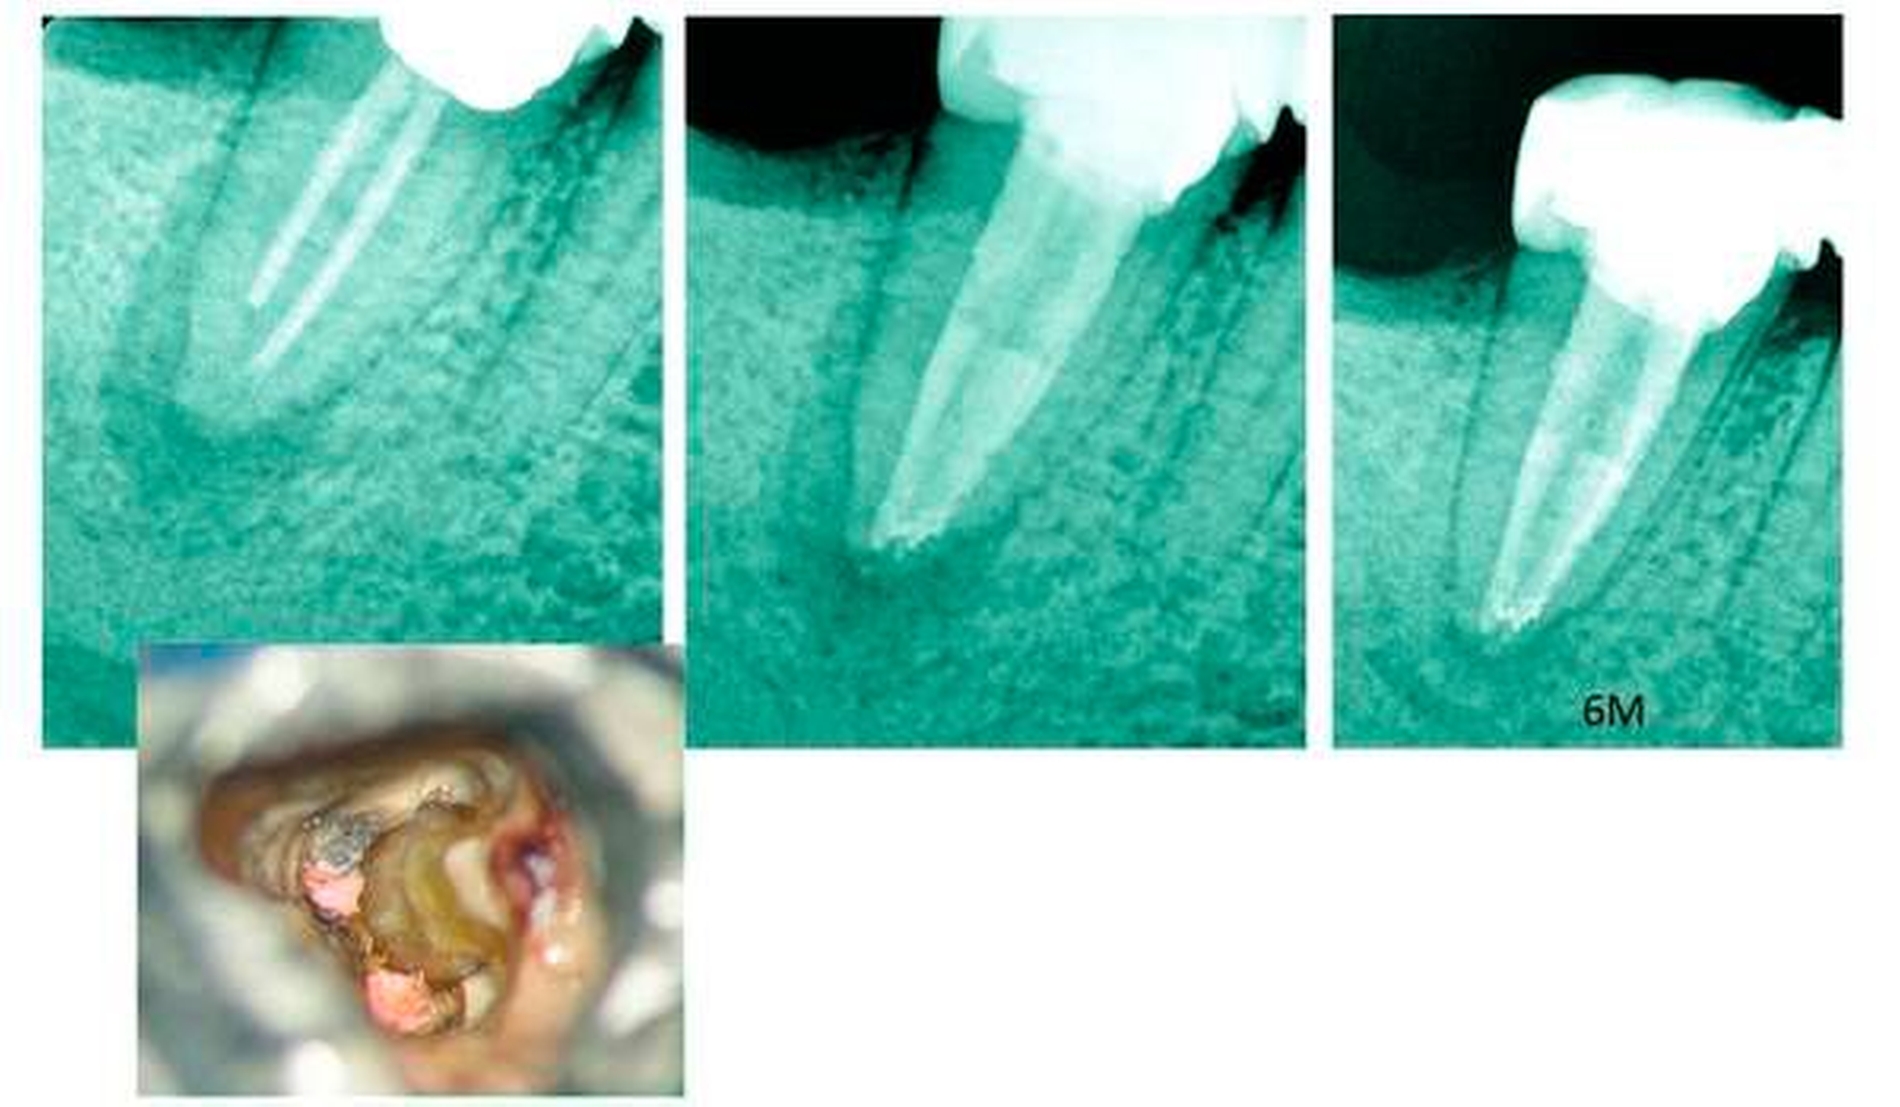

Als sogenannter „middle mesial“-Wurzelkanal wird der zusätzliche Kanal zwischen dem mesiobukkalen und dem mesiolingualen Kanal (der mesialen Unterkieferwurzel) beschrieben (Abbildung 6). Dieser Kanal tritt während der Entwicklung auf [Peiris et al., 2008] und wurde mit einer Häufigkeit von 1 bis 15 Prozent beschrieben [Vertucci et al., 2006]. Durch die Verbesserung der klinisch verfügbaren Detektionsmethoden (zum Beispiel Verwendung des Dentalmikroskops) [de Carvalho & Zuolo, 2000] und dem Abtragen des Dentins zwischen den beiden mesialen Wurzelkanälen bis zu 2 mm wurde in einer neueren Studie eine Prävalenz der mittleren mesialen Wurzelkanäle von bis zu 22 Prozent angegeben [Karapinar-Kazandag et al., 2010] (Abbildung 7). Da jedoch in der Studie das Alter der Patienten zum Zeitpunkt der untersuchten Zahn-Extraktionen nicht bekannt ist, sind die Ergebnisse möglicherweise nicht repräsentativ für die erwachsene Bevölkerung in verschiedenen Lebensphasen. Eine altersbedingte Inzidenz vorhandener mittlerer mesialer Wurzelkanäle wurde von Nosrat et al. [Nosrat et al., 2015] untersucht. Sie fanden etwa 33 Prozent mittlere mesiale Kanäle bei jüngeren Patienten (≤ 20 Jahre), 24 Prozent bei Patienten im Alter von 21 bis 40 Jahren und 4 Prozent bei älteren Patienten (> 40 Jahre). Das Auftreten mittlerer mesialer Kanäle in Unterkiefer-Molaren ist nicht nur altersbedingt, sondern korreliert auch mit verschiedenen Populationsgruppen.

Bei der Identifizierung zusätzlicher mesialer Kanäle in ersten Unterkiefer-Molaren wurde die Anwendung eines Dentalmikroskops oder einer DVT mit der alleinigen Anwendung eines digitalen Röntgenbildes und einer klinischen Untersuchung verglichen. Dabei konnte ein statistisch signifikanter Unterschied gefunden werden: Während eine gute Übereinstimmung zwischen dem Dentalmikroskop und der DVT nachgewiesen werden konnte, war die alleinige Anwendung eines digitalen Röntgenbildes und einer klinischen Untersuchung der Verwendung des Dentalmikroskops oder der DVT beim Auffinden zusätzlicher mesialer Kanäle deutlich unterlegen [de Toubes et al., 2012].